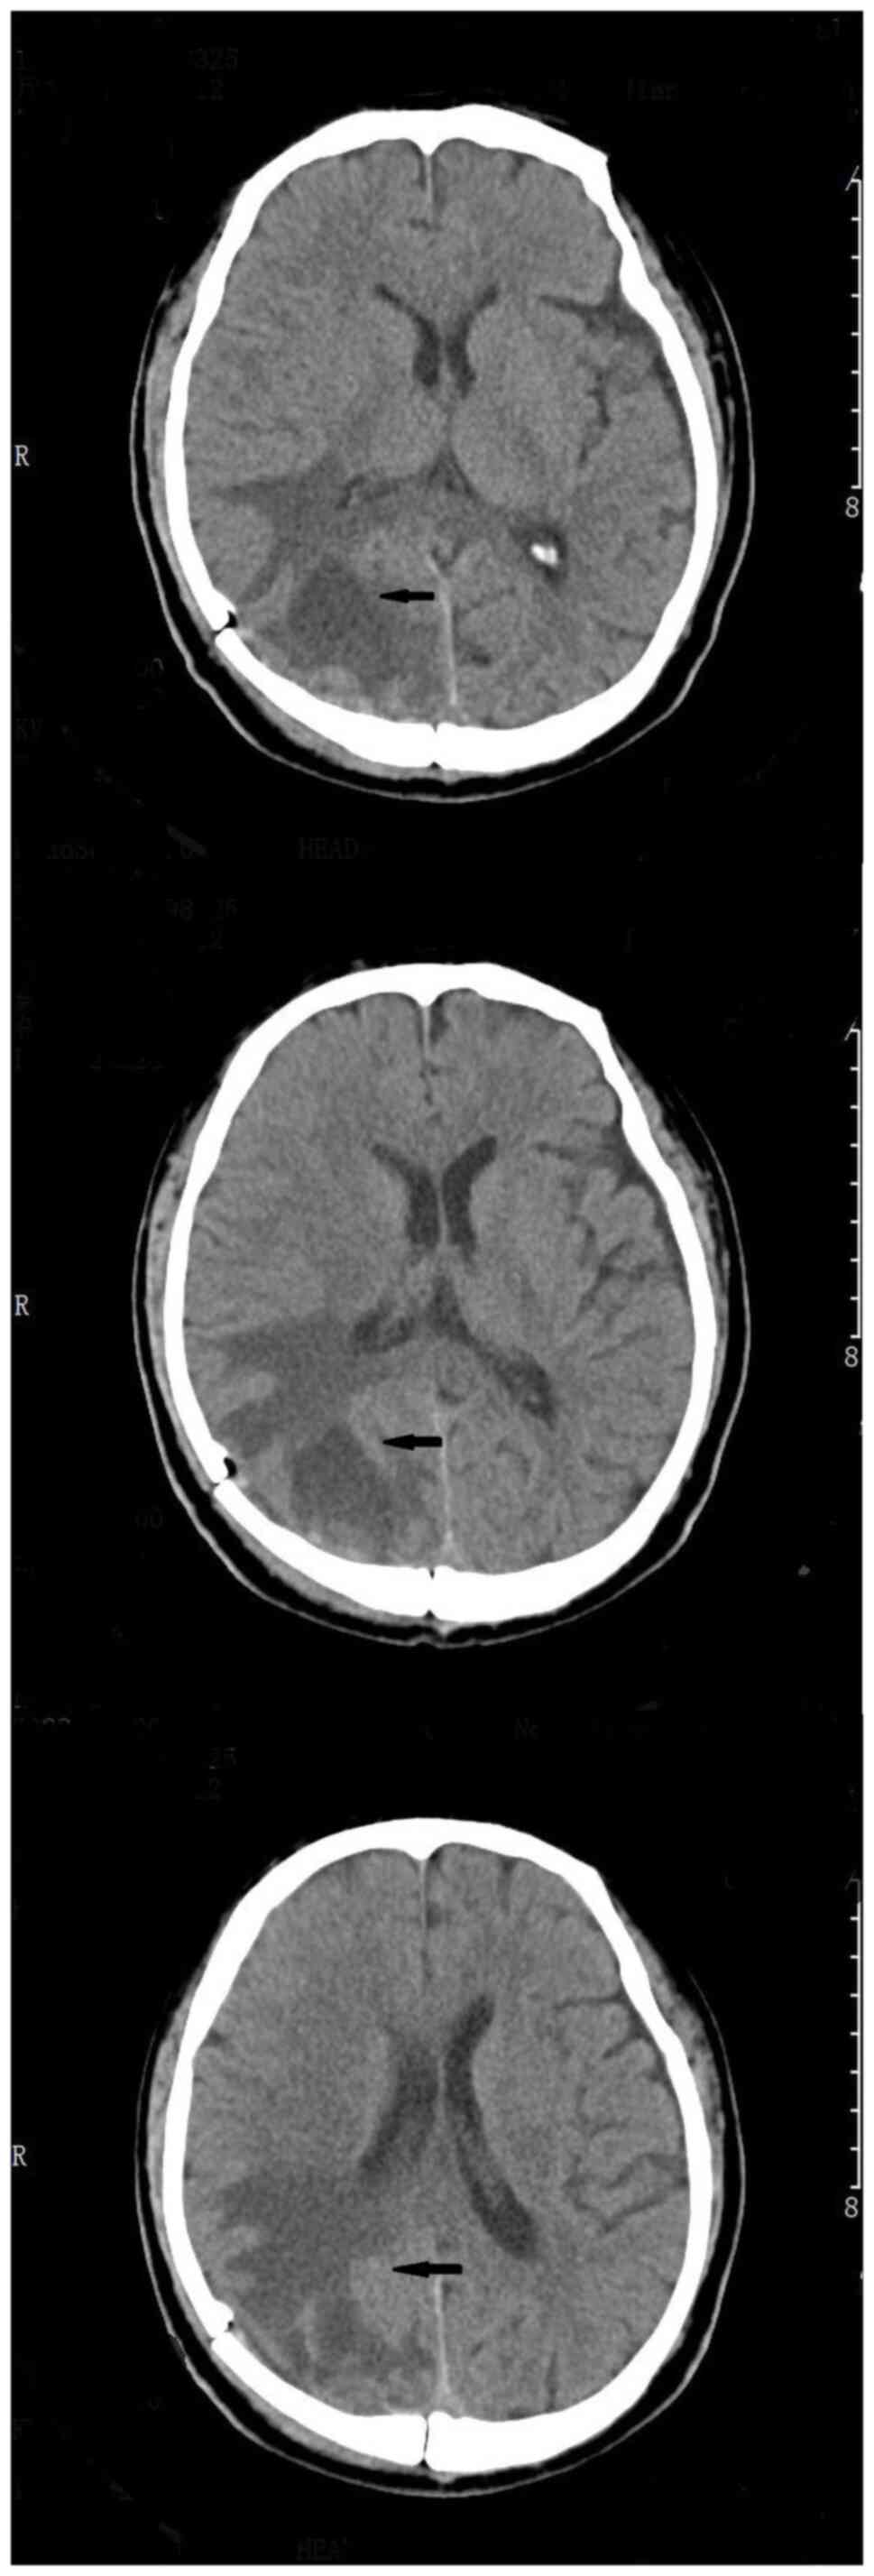

The patient was readmitted on November 28, 2022. Preoperative contrast-enhanced MRI (enhanced T1) of the brain revealed a right occipital lobe mass with increased edema compared to the previous imaging result (Fig. 1), suggesting disease progression. The preoperative lung CT scan did not indicate obvious signs of lung infection and the patient had no obvious respiratory symptoms such as fever, coughing, phlegm, or runny nose. In addition, the patient's routine blood test did not exhibit signs of a bacterial infection. Finally, the patient underwent surgical treatment. During the procedure, a few pale-yellow changes were observed on the brain surface and the adhesion of the space-occupying lesion to the surrounding brain tissue was obvious with a thick capsule containing pus. Some of the pus was taken for NGS and culture, and the capsule tissue was sent for routine pathological examination (Fig. 2).

Figure 1

Head magnetic resonance imaging (enhanced T1) of the patient was performed before the operation. The arrow in the picture indicated an intracranial occupying lesion that was considered in the right occipital lobe, but the edema was worse than before, indicating that the disease had progressed.